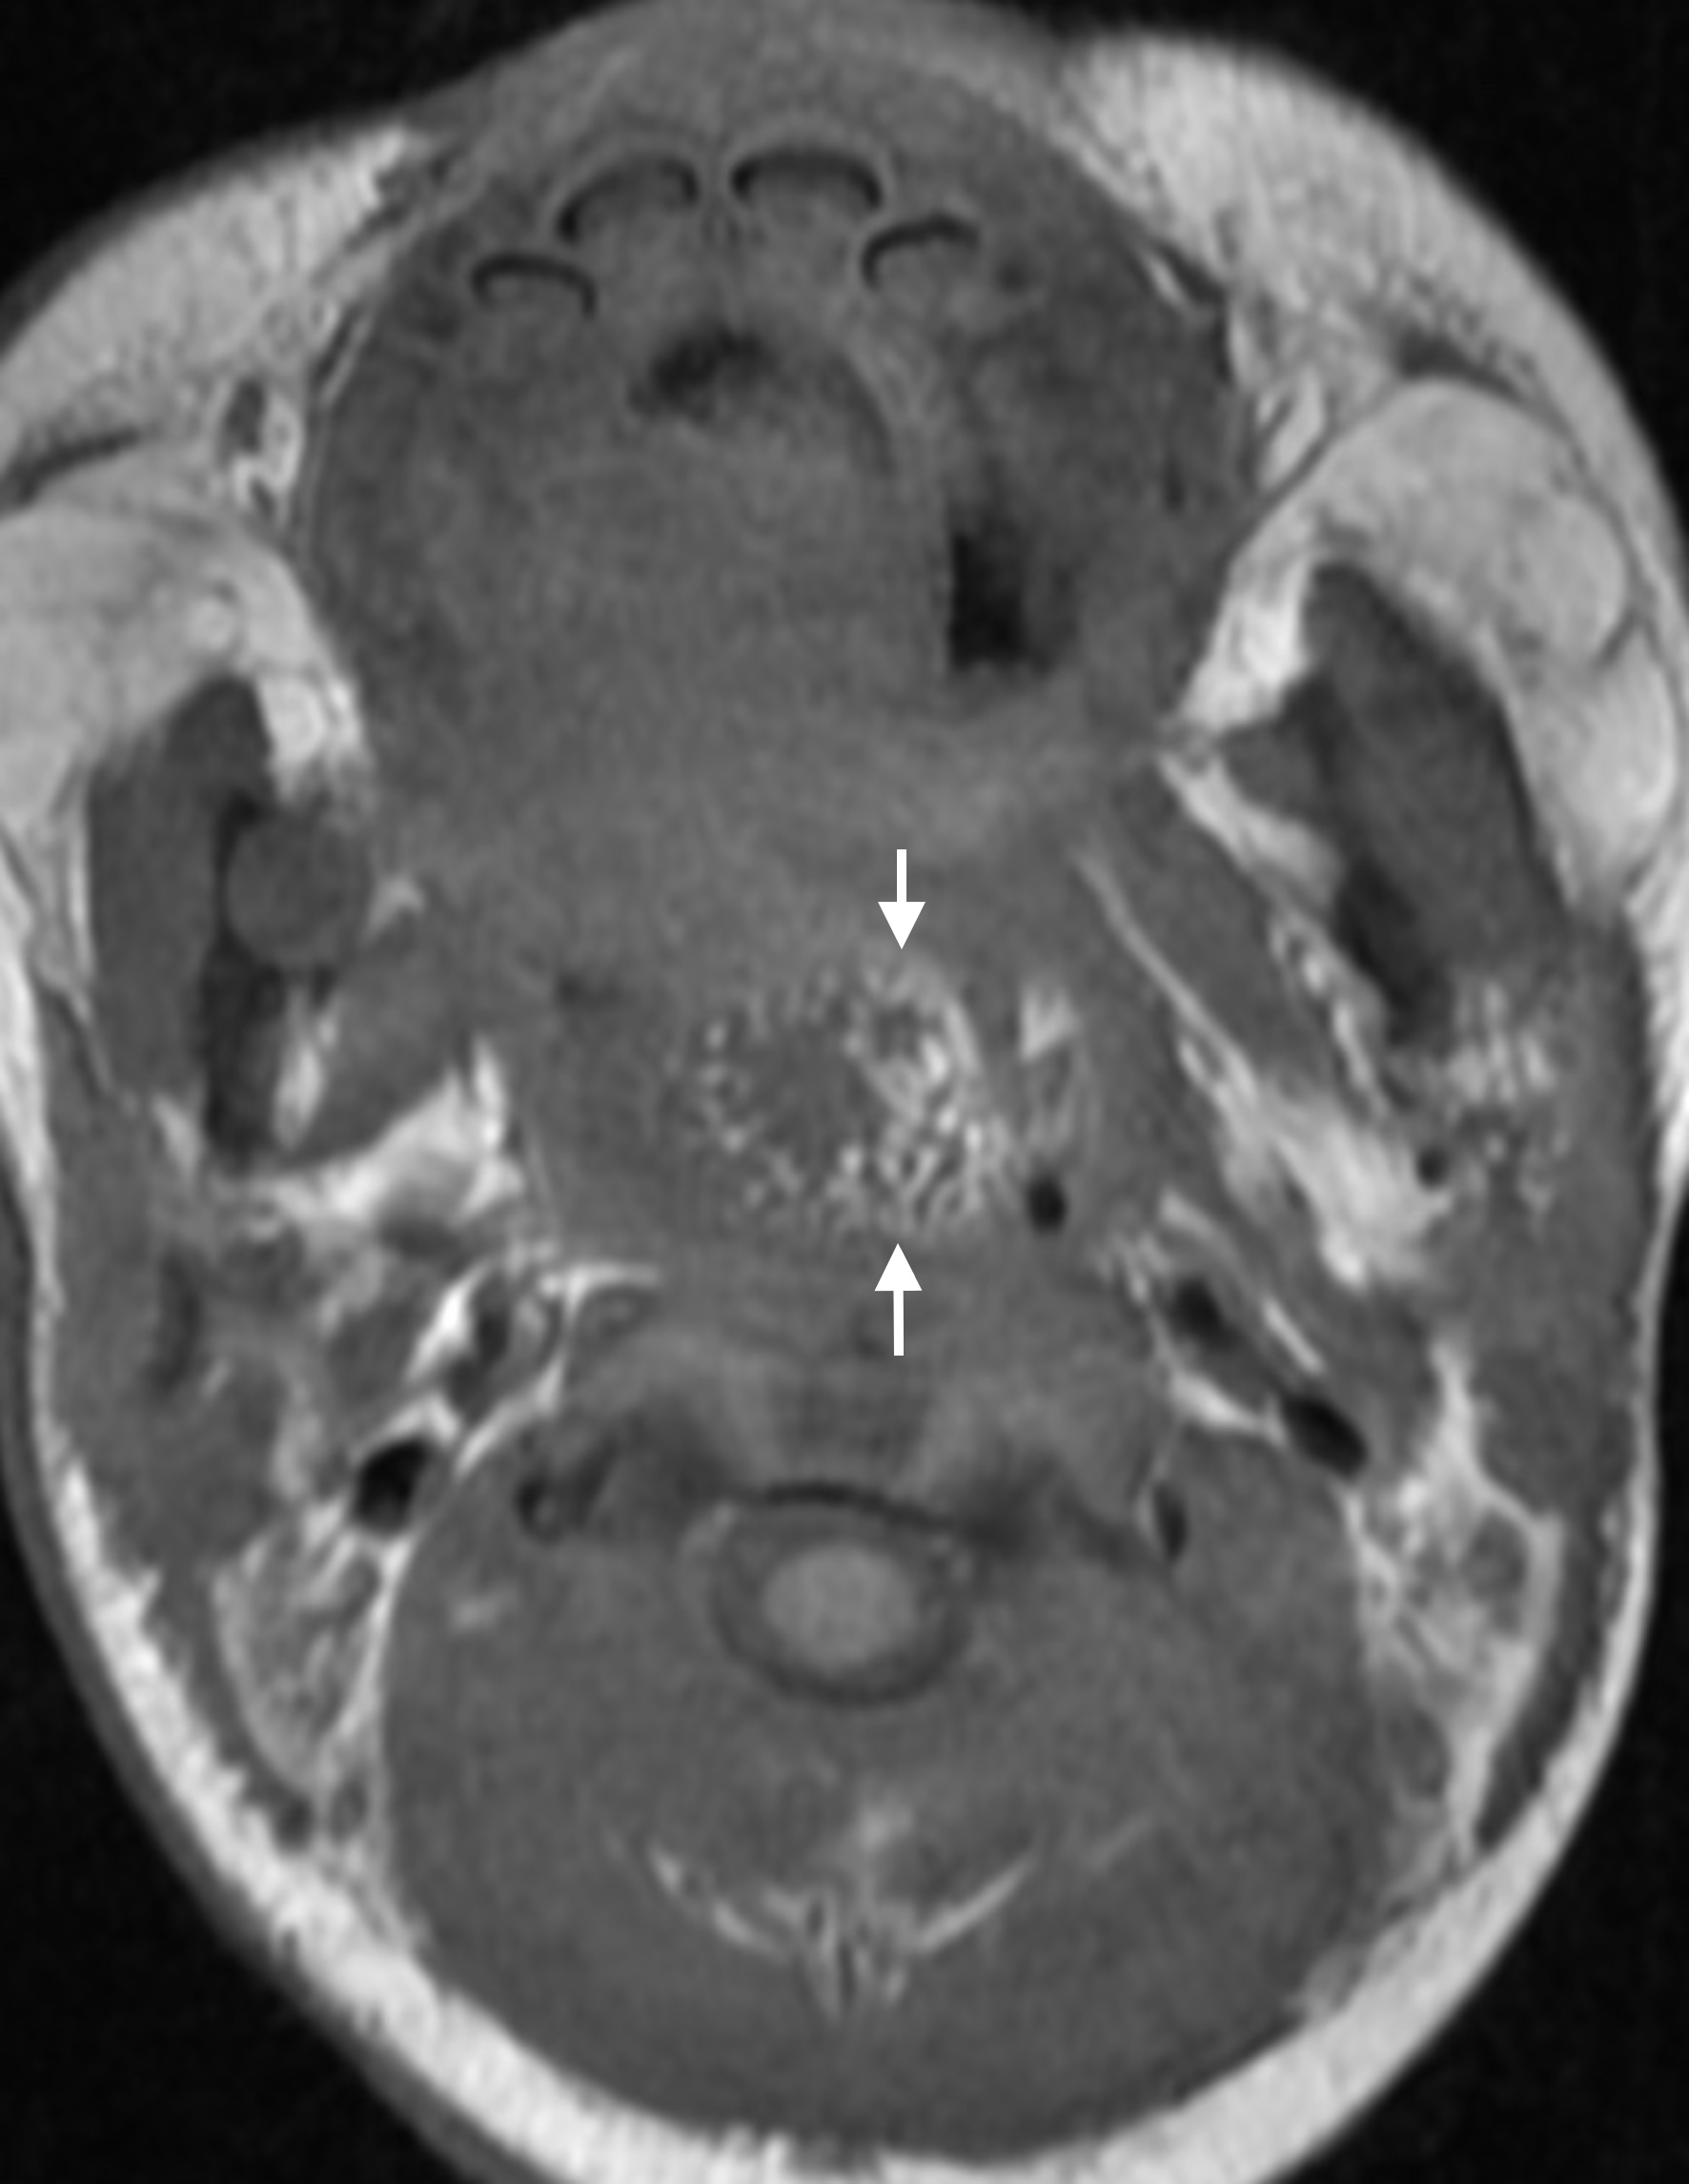

Pharyngeal hairy polyps are rare lesions that arise from the nasopharynx or oropharynx. It occurs predominately in females, with predilection for the left side. Its etiology remains poorly understood. It typically presents in the neonatal period with respiratory distress and feeding difficulties. Imaging is fundamental to identify the high fat content of the lesion. Surgical resection is the treatment of choice. We report a case of a nasopharyngeal hairy polyp causing respiratory distress since birth.